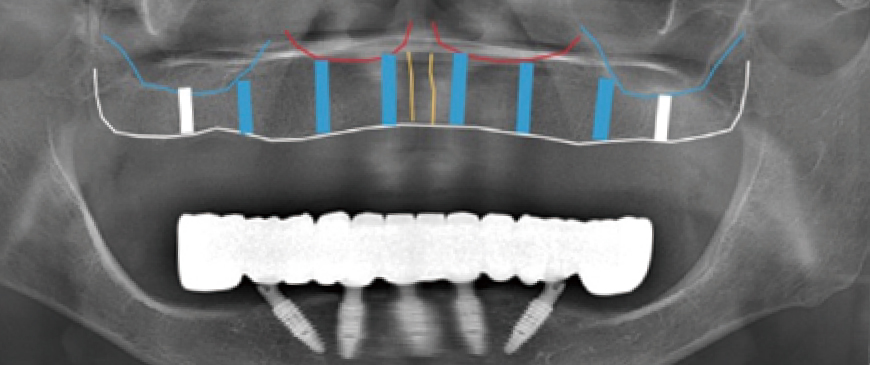

Post-surgery panoramic radiograph. Immediately after the surgery, impressions were taken to prepare provisional prostheses.

Fig 9

Post-surgery CBCT radiograph. All ARi implant threaded parts were properly positioned within the alveolar bone